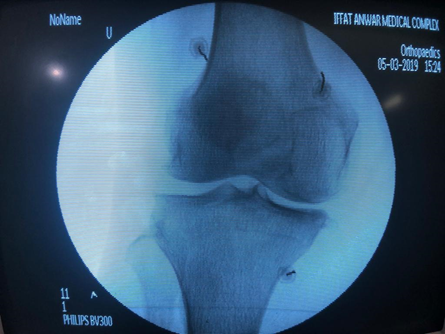

RF Rhizotomies of Genicular Nerves procedure.

RF Needles position in AP view.